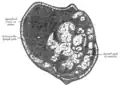

Section of small lymph node of rabbit. X 100. -